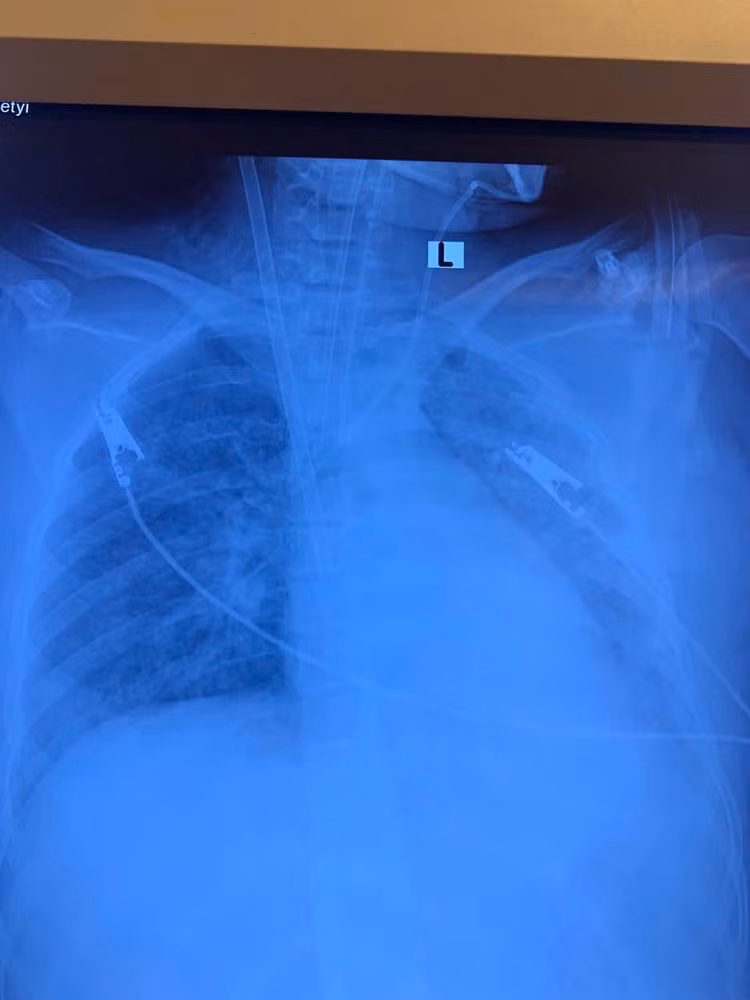

Bệnh nhân nữ, 19 tuổi, nhập viện trong tình trạng khó thở, sốt cao, ho đờm. Chẩn đoán ban đầu là viêm phổi nặng. Chỉ trong vòng 3 ngày, tình trạng hô hấp suy sụp nhanh chóng, hình ảnh X-quang và CT phổi cho thấy phổi trắng xóa hai bên – dấu hiệu điển hình của Hội chứng suy hô hấp cấp tiến triển (ARDS), một biến chứng nguy kịch thường gặp ở những ca viêm phổi nặng.

Hình ảnh tổn thương phổi trên phim chụp - Ảnh BVCC